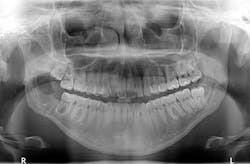

Clinical examination revealed inflamed tissue circa partially erupted No. 32 extending up to the distal of no. 2. The area intraorally was tender to palpation, but unremarkable extraorally. A panoramic X-ray was taken and a large radiolucent lesion was noted to extend from the distal of no. 1 to the distal of no. 32. A significant portion of bone destruction in the mandible was also observed. In addition, a radiolucency was seen distal to the crown on no. 17.

The patient was sent to surgery for enucleation and curettage of the lesion. Differential diagnoses included: unicystic ameloblastoma, odontogenic myxoma, and dentigerous cyst.